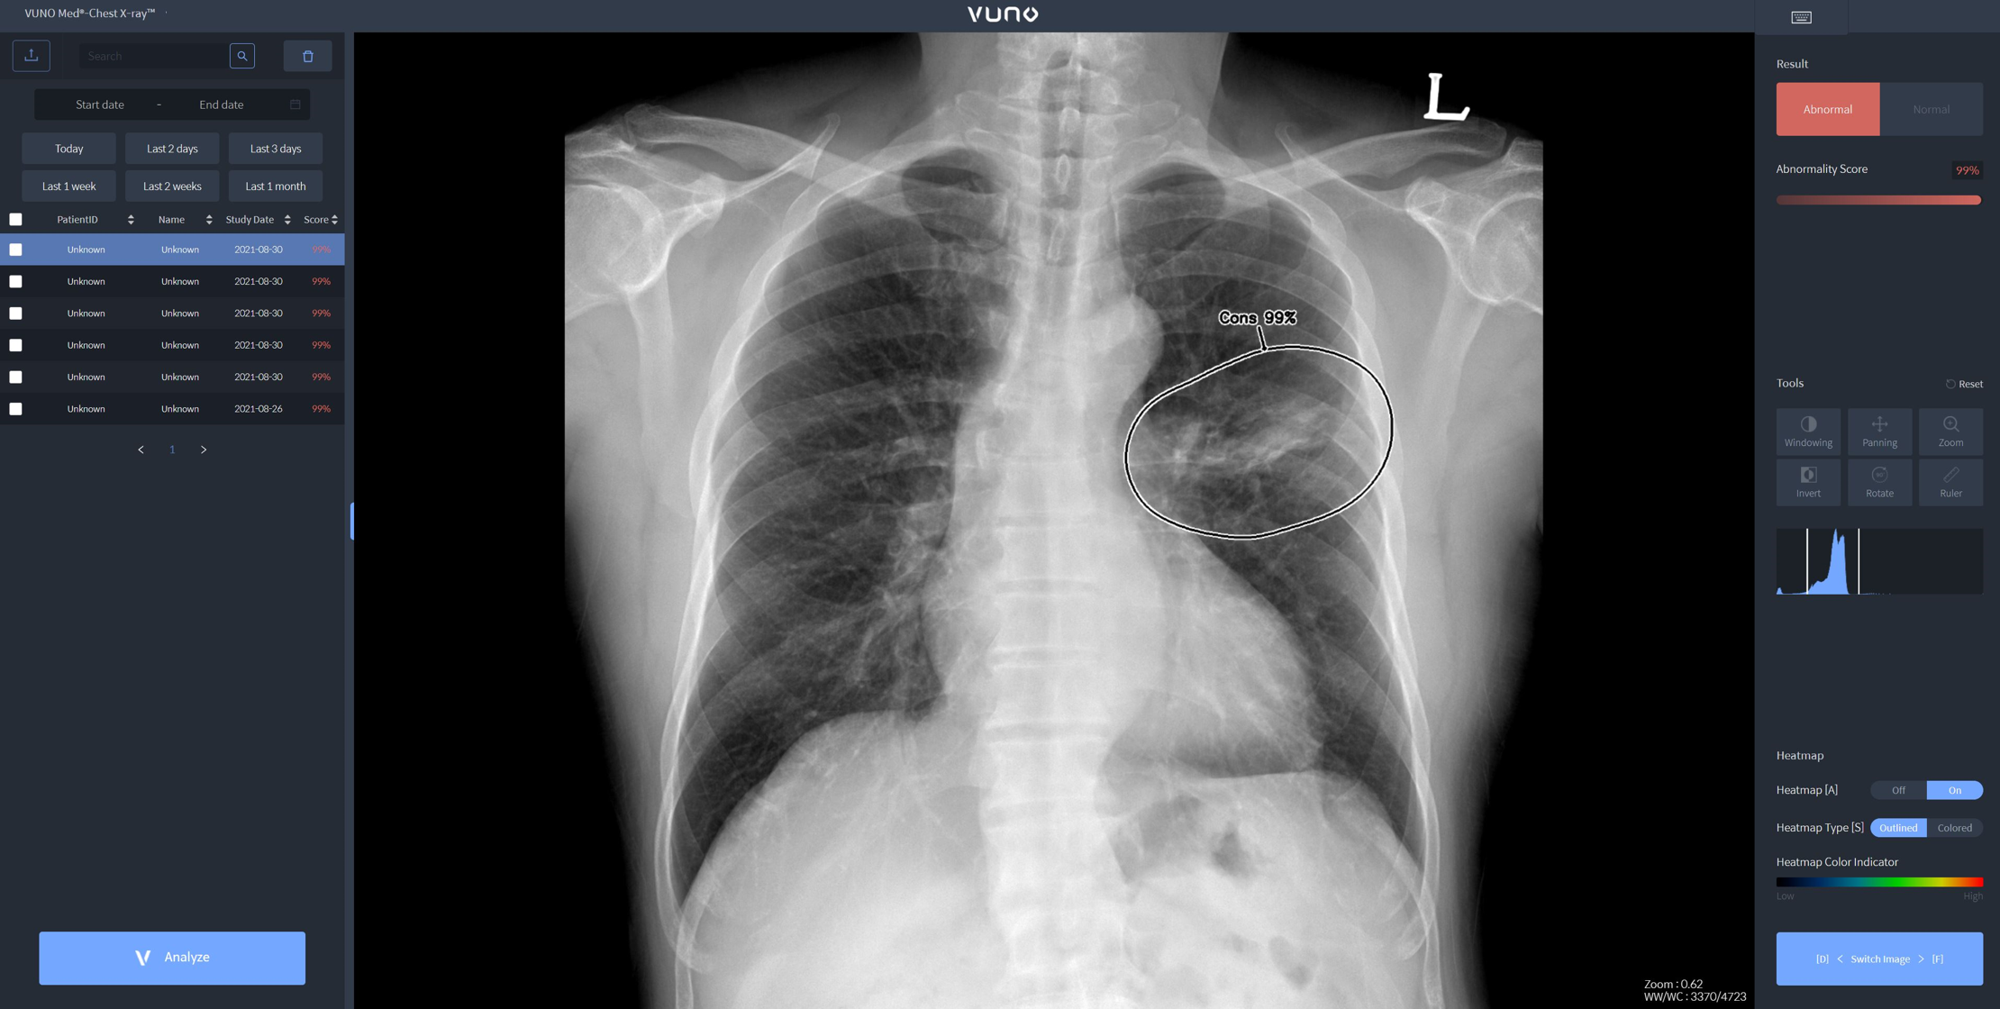

이번 태국 허가를 획득한 뷰노메드 체스트 엑스레이는 흉부 엑스레이 영상에서 결절, 경화, 간질성 음영, 흉수, 기흉 등 주요 이상소견을 높은 정확도로 탐지하는 인공지능 솔루션이다. 의료진에게 이상소견의 소견명과 위치를 제시해 결핵, 폐렴 등 주요 폐 질환 진단을 돕는다.

해당 솔루션은 영상의학 학술지인 Radiology에 게재된 임상연구에서 높은 판독 정확도와 효율성을 입증한 바 있다. 국내외 주요 중대형병원에서 활발하게 사용되며 임상적 가치가 검증된 주요 제품 중 하나다.